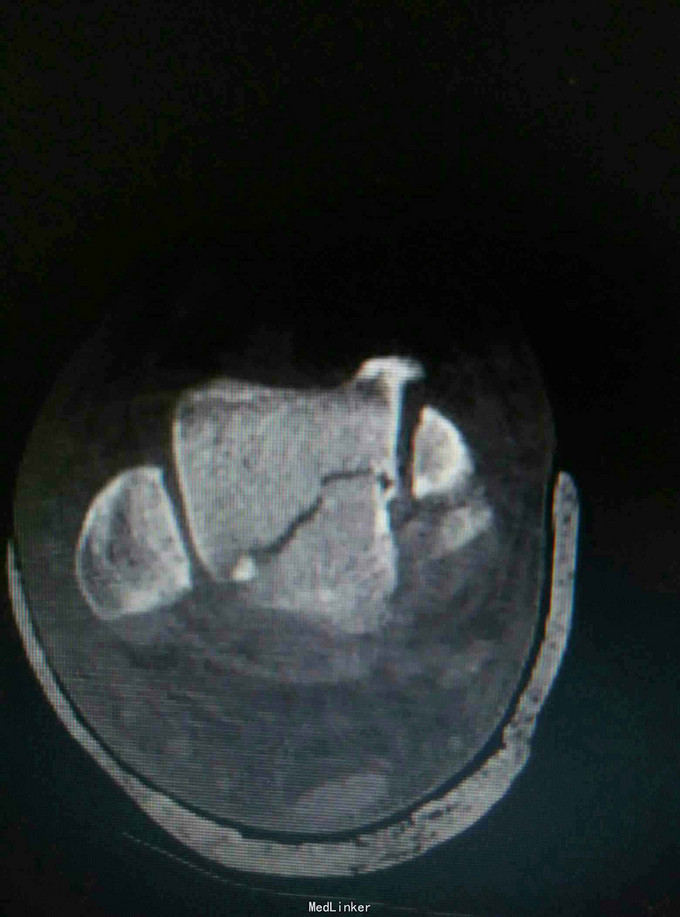

患者,男,45岁,车祸伤致右踝部肿痛,活动受限2小时入院

入院查体见局部肿胀,予完善影像学检查,

诊断是右距骨粉碎性骨折。给予行内踝截骨显露骨折端进行复位,采用Herbert钉进行固定。

术后复查X线片提示骨折端完全复位,内固定固定在位良好。 讨论:距骨骨折的主要并发症是坏死,骨不愈合等,但近年来随着对其认识的不断明确,治疗比较规范,积极的进行切开复位,并行坚强固定,近年的研究报告提示距骨的坏死率是不断在下降的,当然前提是进行有效复位并坚强固定。